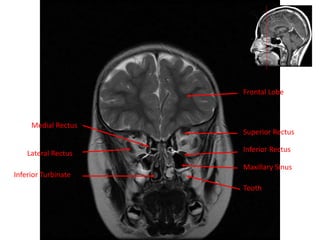

Medial Rectus

Frontal Lobe

Lateral Rectus

Inferior Turbinate

Superior Rectus

Inferior Rectus

Maxillary Sinus

Tooth